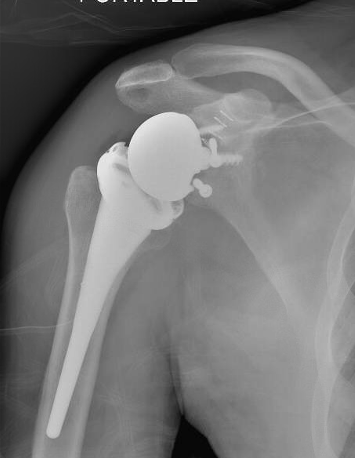

Post humeral head replacement / glenoid autograft / rotator cuff repair

Rotator cuff failure and development of anterosuperior escape